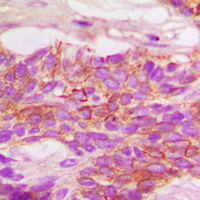

IHC (Immunohiostchemistry)

(Immunohistochemical analysis of HER2 (Phospho-Y1248) staining in human breast cancer formalin fixed paraffin embedded tissue section. The section was pre-treated using heat mediated antigen retrieval with sodium citrate buffer (pH 6.0). The section was then incubated with the antibody at room temperature and detected using an HRP conjugated compact polymer system. DAB was used as the chromogen. The section was then counterstained with haematoxylin and mounted with DPX.)